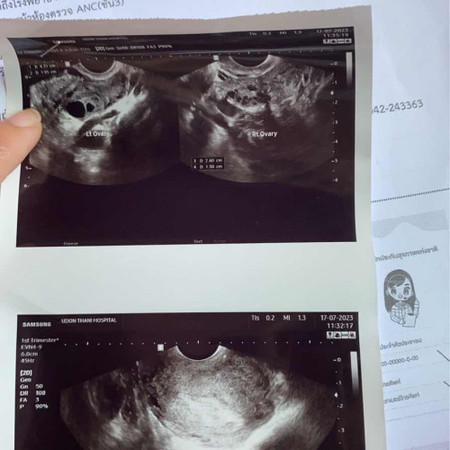

บ้านนี้คะแนว่า 12wคือประจำที่มาครบ แต่เรานับประจำเดือนครั้งสุดท้าย ที่มา1วัน ประมาน6w ไปซาวด์มาวันนี้ ยังไม่เจอน้องเลยคะ ได้ส่งตัวไปโรงพยาบาลในเมือง หมอบอกว่าเหมือนเห็นก้อนอะไรไม่รู้ที่ ปีกมดลูกข้างขวา รอไปวันนัดที่26นี้คะ

บ้านนี้พึ่งไปซาวด์มาวันนี้เลยคะ 7+6 ยังไม่เจอตัวน้องเหมือนกัน เจอแต่ถุงตั้งครรภ์กับไข่แดงหมอนัดซาวด์อีก2สัปดาห์ แม่ไม่ต้องกังวลน้า ลุ้นๆไปพร้อมกันค่ะ😹❤️

เหมือนกันค่ะแม่ ประจำเดือนครั้งสุดท้าย 4 มิถุนายน ไปซาวด์เมื่อวานเจอแต่ถุงตั้งครรภ์ไม่เจอน้อง กังวลใจเหมือนกันค่า

พึ่งผ่านมาเลยค่ะ ตอนแรกหมอบอกเสี่ยงท้องลมค่ะไม่เจอตัวเด็กแต่เจอถุงกลมๆด้านในแต้อายุครรภ์จากปจด.มัน7สัปดาห์แล้วค่ะ หมอเลยนัดอีกที2สัปดาห์ พอมาซาวอีกทีเจอแล้วค่ะ อายุครรภ์พึ่งจะ7สัปดาห์5วันค่ะตอนซาวเจอ หมอวัดจากขนาดถุงและขนาดเด็ก สรุปปจด.ไม่ตรงกับอายุครรภ์ตอนแรกค่ะ เคลื่อนไปหน่อยค่ะ

ซาวด์ตอน5วีคก็ไม่เจอค่ะ เจอแค่ถุงตั้งครรภ์ แต่ซาวด์ตอน7วีคเจอน้องแล้วค่ะ ผ่านช่องคลอดทั้งสองรอบ